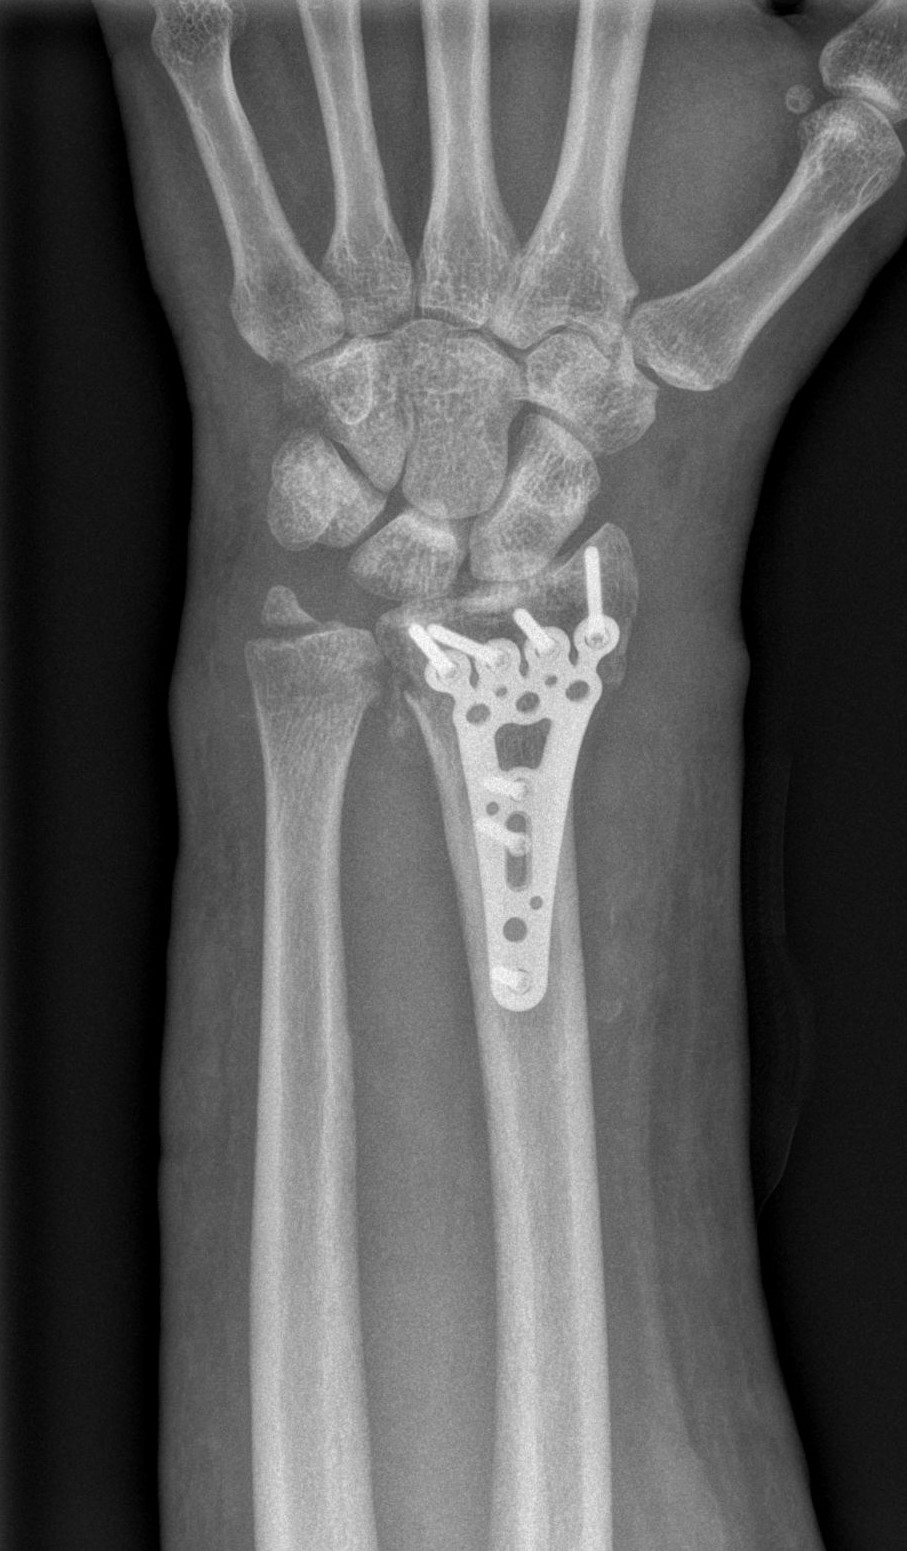

Treatment of neglected, displaced or united distal radial fractures (DRFs) is difficult, because it requires either wedging the almost consolidated fracture and reduction to the correct position, or cutting the united bone and putting it in the correct position (corrective osteotomy). Both treatments are associated with the risk of failure and complications. The paper presents a case of almost fully united DRF in a man, in whom 5 weeks after the injury, and after unsuccessful primary fixation with K-wires, the bone fragments were surgically wedged, aligned and fixed with a palmar plate. The result of treatment after 2 months was satisfactory. Early surgery allowed for a significant shortening of the recovery period and allowed the patient to return to work.